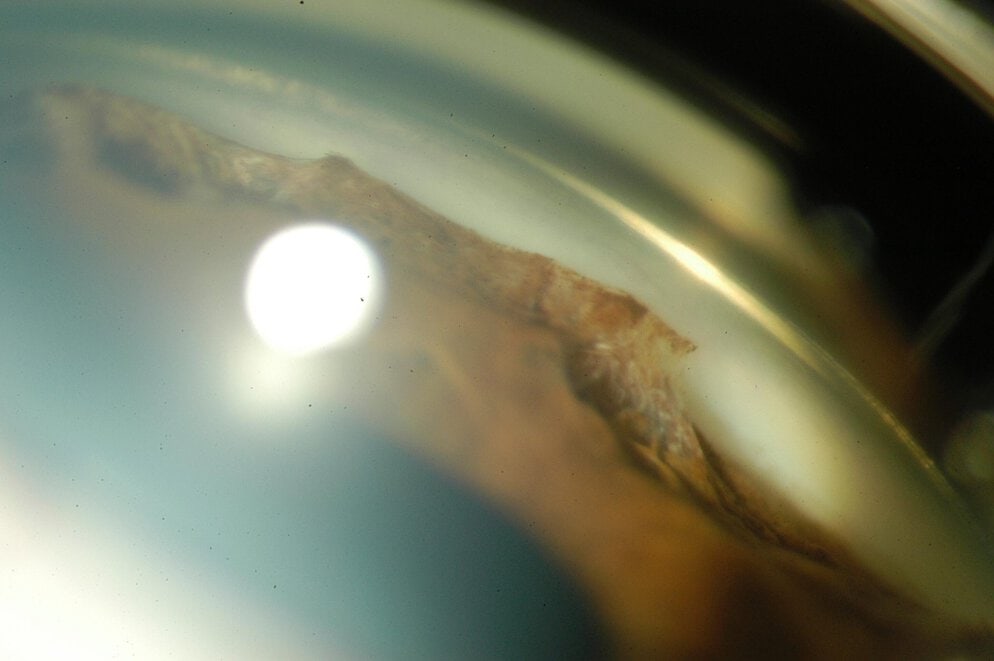

Synéchie dans un ICE syndrome

Le syndrome irido-cornéo-endothélial (ICE), qui englobe l’atrophie essentielle de l’iris, le syndrome de Chandler et le syndrome de Cogan-Reese (ou “iris nævus syndrome”), est le plus souvent unilatéral, non familial et survient typiquement chez la femme jeune. Le syndrome ICE est généralement progressif et se complique fréquemment de glaucome secondaire et de décompensation cornéenne. Dans le syndrome de Chandler, les anomalies iriennes sont moins marquées, et l’œdème de la cornée est plus important que dans l’atrophie essentielle de l’iris ou le syndrome de Cogan-Reese.

(Cliché dû à l’amabilité de Rouland JF, Lille)